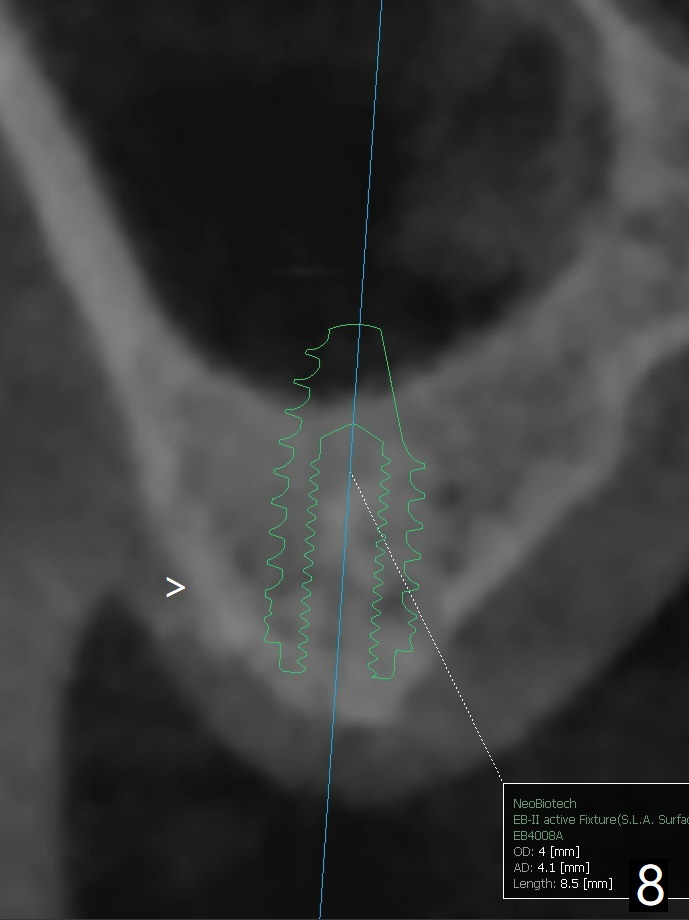

当3号牙短小植体植入后(图一(骨质密度高)),病人纳闷为什么不给他装临时牙冠,术后两个月又打电话要求提前修复,因为放置愈合基台,他无法使用局部托牙(单个牙),而14号牙即刻植牙即刻修复。他无法理解我们苦衷,有什么补救方法?

使用来自钻头的自体骨做提升,植体植入后,颊侧骨板薄,刚好骨下。使用5.5毫米profile drill后,放置愈合基台,术后三个月脱落,他再次要求修复,甚至提出退款,不愿意回诊所,因为他有糖尿病,新冠病毒高危人群。 放置小号愈合基台(图二)。他原来托牙是Valplast,没有occlusal rests,不能经过修改临时使用,可能将直接放置修复基台做临时牙冠。放置修复基台后(图三(术后三个月)),制作临时牙冠时,发现前者有些松动,后者就没有粘固。当基台完全就位,它最冠方与植体没有间隙(箭头),根方有间隙(空心箭头)。其实愈合基台也是一样(图一,二)。后来植体松动(术后4个月),拔除,植骨(图四),颊侧骨板缺失(图五:B)。植骨后5个月2号牙疼痛需要拔除种植(图七),与3号牙一起种植(图六),颊侧骨板修复,但是高度有所下降(箭头)。The narrow ridge with the intact buccal plate (Fig.8 >) can hold a 4x8.5 mm implant. The buccal plate is lost 4 months postop (Fig.9) and restores 5 months post graft (Fig.10). Return to Upper Molar Immediate Implant, No Deviation Coronal and Apical Gap in IBS implant Protect Graft Xin Wei, DDS, PhD, MS 1st edition 06/22/2020, last revision 05/02/2021